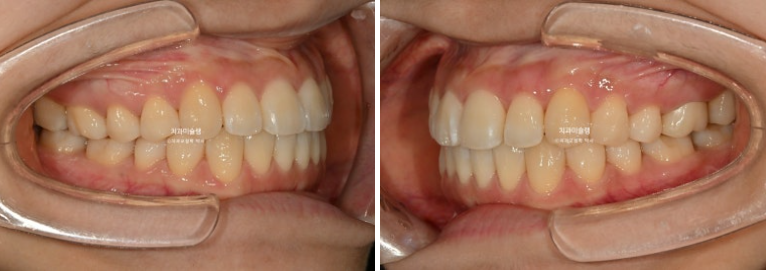

25.03

중심선 불일치, 덧니, 반대교합 등이 보입니다.

절단교합도 보이고

앞니쪽은 뒤죽박죽이나 그에 비하면 어금니 교합은 아름다운 1급 교합관계를 보입니다.

25년 3월부터 8월까지 첫세트 14개 장치를 모두 낀 후 모습입니다.

25.08

덧니 개선을 위한 고무줄 처방이 함께 들어갔으며, 메탈 고리는 고무줄 거는 고리를 치아에 붙여놓은 것 입니다.

반대교합은 해소가 되었지만 아직 중철치 - 측절기간 단차가 보이는 상태입니다.